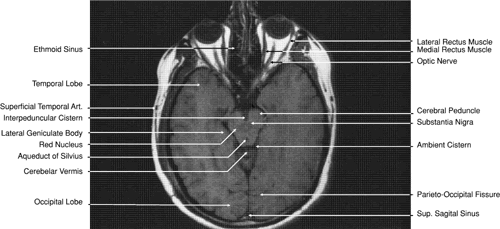

The globe is shown in Figure 12. The orbit and periorbital structures are shown in Figures 13 through 16, and the optic canal is shown in Figures 17 through 26. The cavernous sinus and optic chiasm are shown in Figures 27 and 28, and the posterior visual pathway and cranial nerves are shown in Figures 29 through 33.

Fig. 31. Axial T1-weighted image through the cerebral peduncle at the level of oculomotor nerve.

Fig. 32. A. Axial computed tomography soft tissue image at the level of suprasellar cistern. B. Axial computed tomography soft tissue image at the level of thalamus. C. Axial T1-weighted image at the level of thalamus.

Fig. 33. Sagittal T1-weighted image of the brain through the interhemispheric fissure.